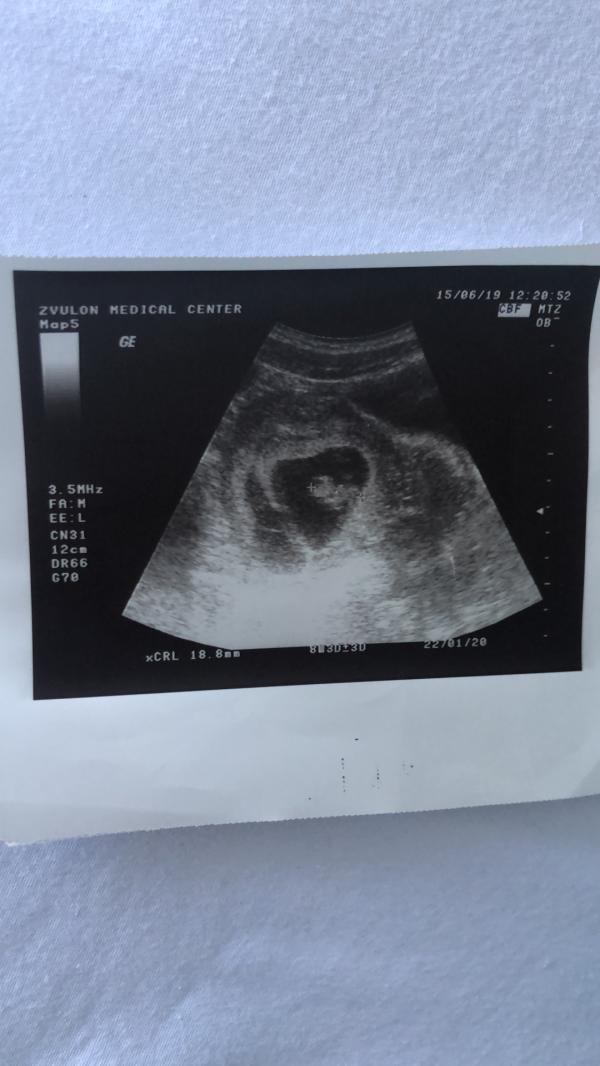

На 8-мой недели мы поехали в частную больницу с лучшем оборудованием какое у них есть, а оно у них старенькое кстати. Нам показали плод, нам сказали что есть сердцебиение, правда мы его не услышали, но врач НЕ УВИДЕЛА второй плод🤦🏻♀️. На фото от УЗИ и правда не видно второго плода, но видно второй мешочек, он маленький и я не придала ему значения.